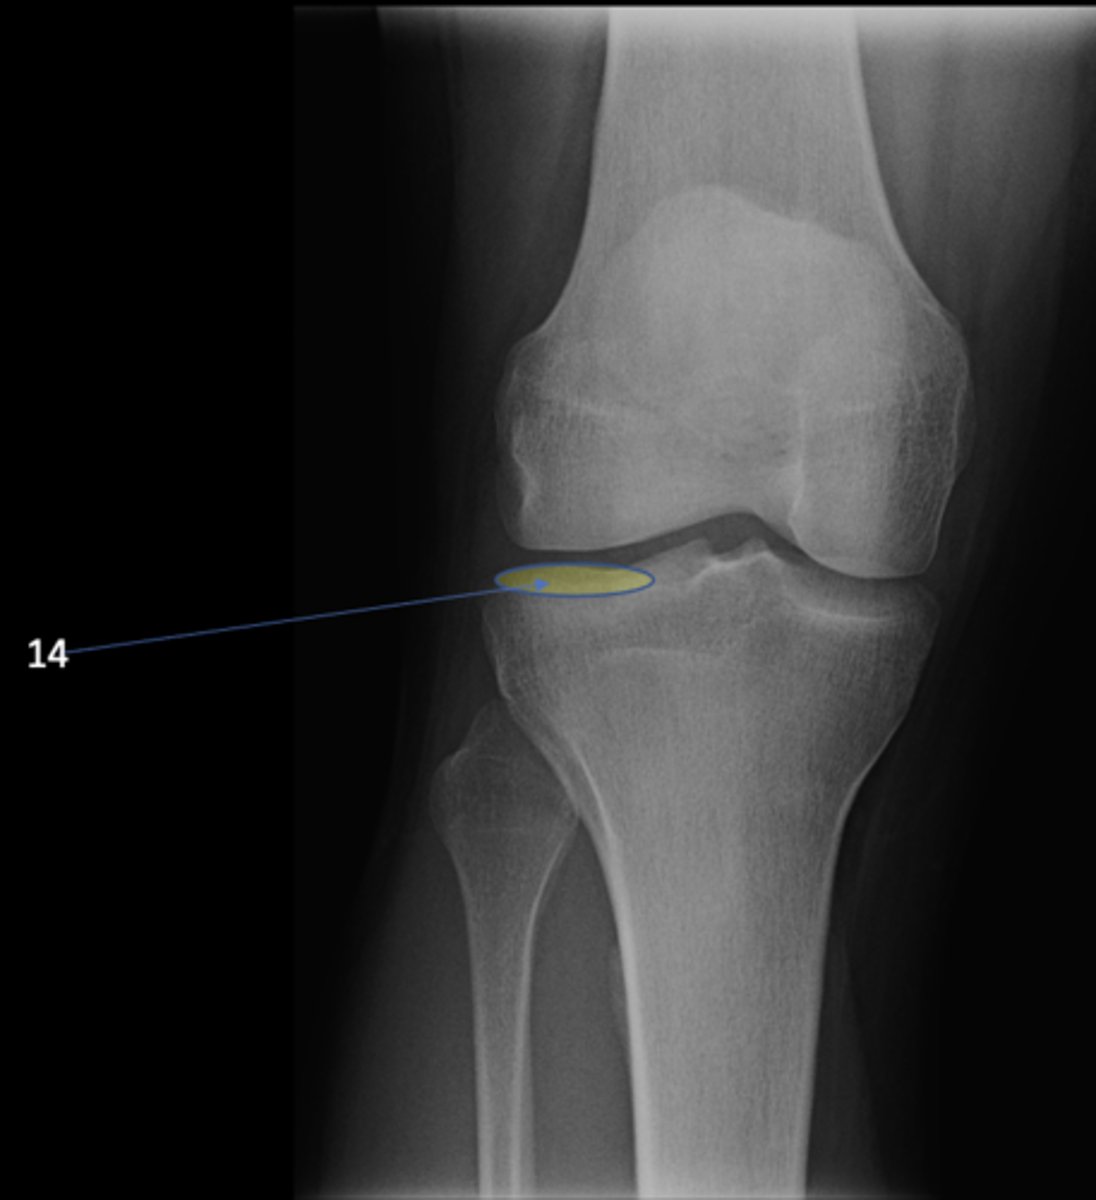

8

New cards

Left ischial spine

ID 8

<p>ID 8</p>

9

Right fovea capitis

ID 9

<p>ID 9</p>

10